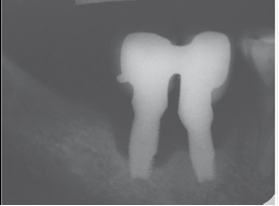

Control Radiográfico. Hubo coincidencia entre todos los autores sobre la importancia del control radiográfico de los implantes en el tiempo. La discrepancia fundamental se centra en la oportunidad de obtener la radiografía inicial: al momento de la colocación del implante, cuando se instala la rehabilitación o posterior al remodelado óseo. Este taller encontró mayor evidencia científica, así como coincidencia entre los autores, que sugieren el control radiográfico inicial, luego del remodelado óseo post rehabilitación11,13,14.